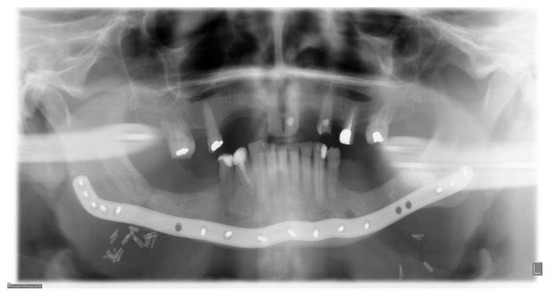

Immediate postoperative situation captured with CBCT.

Figure 12.

Six months follow-up. Clinical and radiological healing is seen in the previous fracture areas in the region of the first molar on both sides of the mandible.